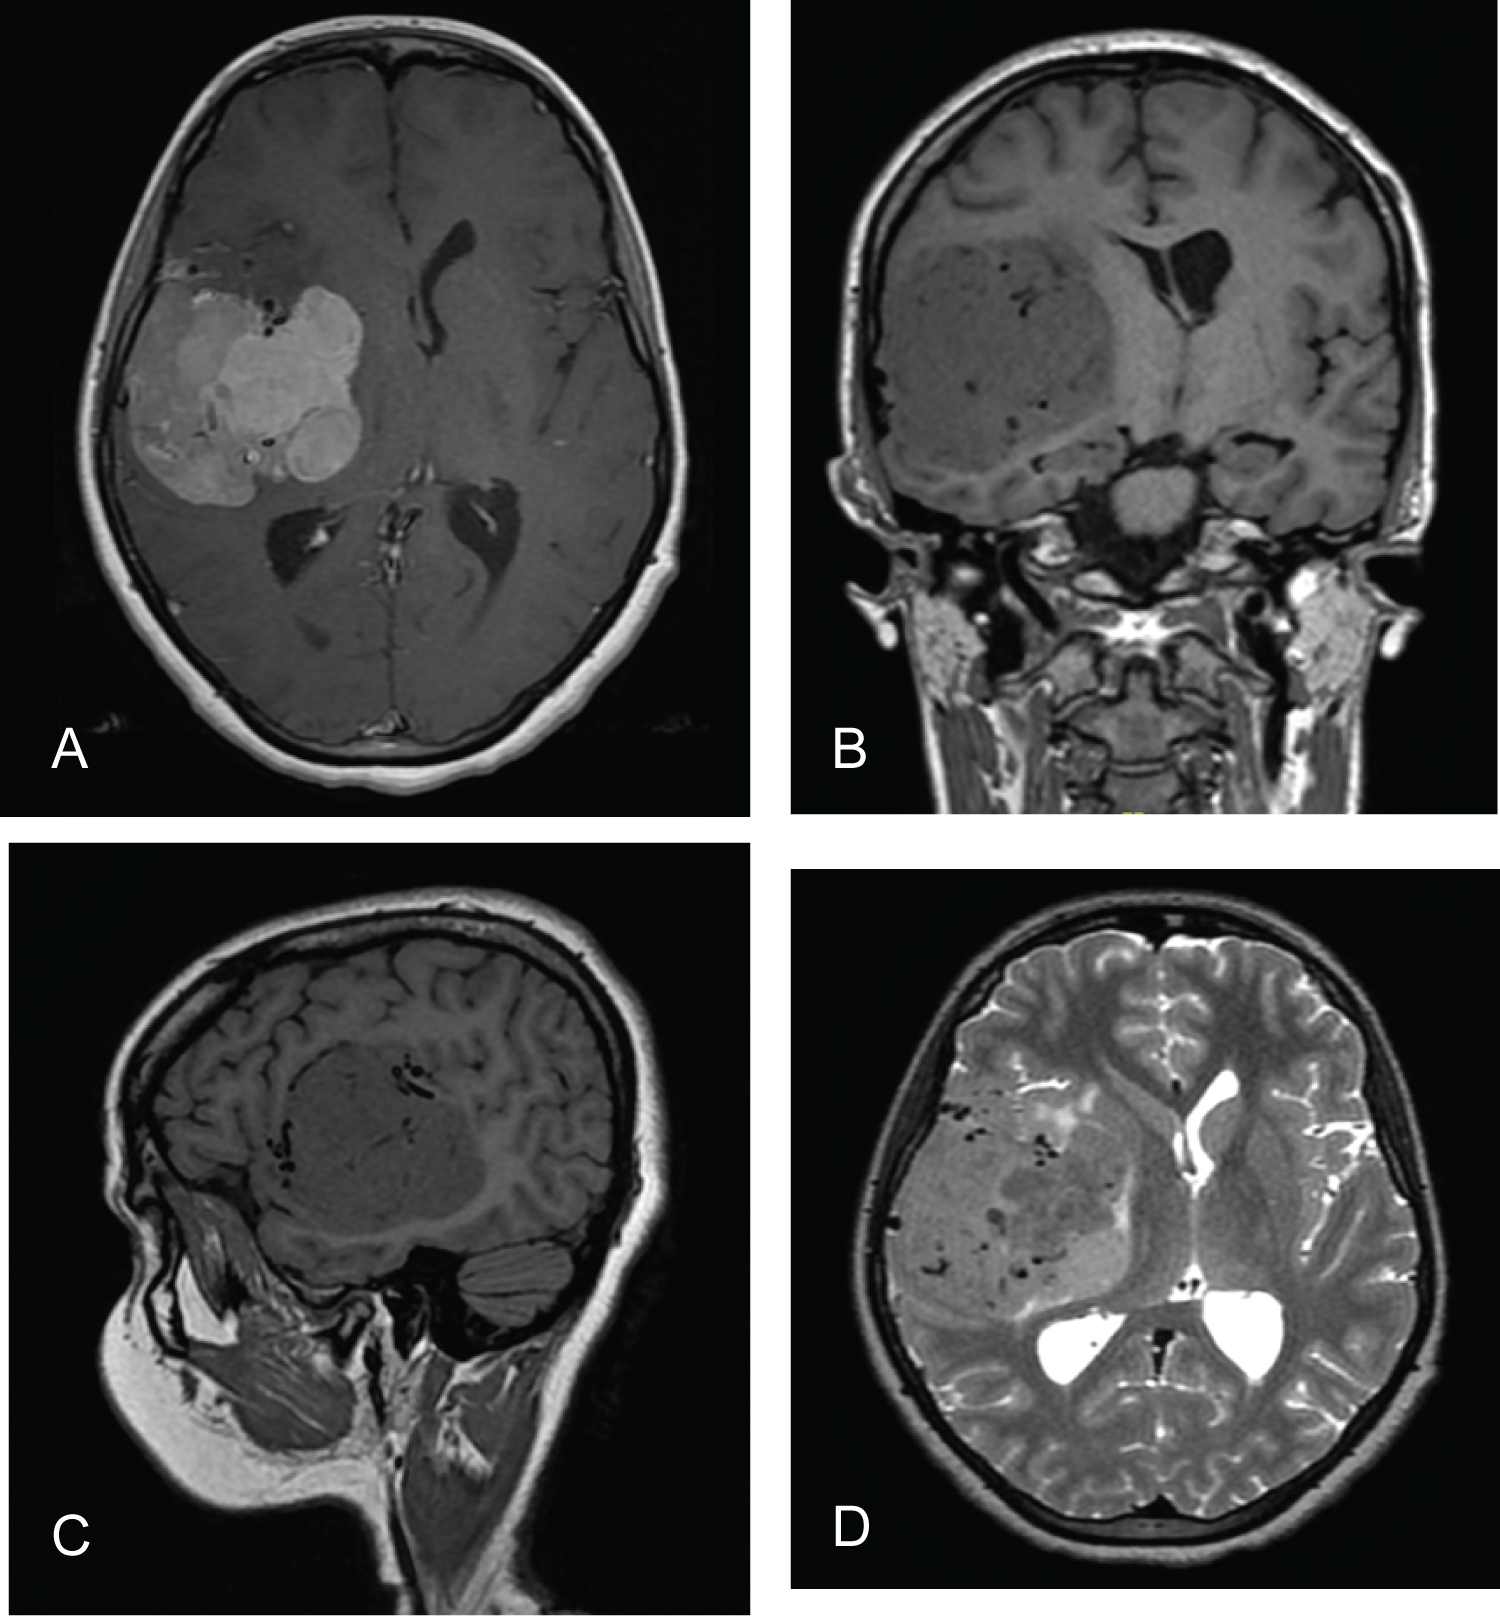

Postoperatively, the patient was kept in the neurocritical care unit (NCCU), where she was sedated and intubated as elected by the anesthesia team due to the long operating time. The next morning, she was still intubated, off sedation and maintaining a Glasgow Coma Scale of 11/15 with reactive pupils, and she could move all limbs freely. On postoperative day 2, she was shifted to the floor with a GCS of 15/15 and no motor or sensory deficits. MRI was obtained (Figure 3); there was debulking of the large lesion in the right frontotemporal area, and residual tumor tissue was seen along the margins of the cavity. There were no territorial ischemic changes. Prior to discharge, cerebral angiography was performed to evaluate the patency of the vessels and to exclude any major radiographic stenosis (Figure 4).

Figure 3: Postoperative MRI showing significant debulking of the tumor with small residual (Arrows) and expected postoperative changes. There were no territorial ischemic changes. (A) Axial view of contrast-enhanced T1WI; (B) Coronal view of contrast-enhanced T1WI. View Figure 3

We observed the patient with close follow-up to reassure her about the pathology, as it resulted in WHO grade 1 meningioma. Her seizures were controlled on levetiracetam, and she returned to her normal daily activities. The fact that there was residual tumor tissue that needed to be followed with MRI was explained. She returned 3 and 9 months after surgery, and follow-up MRI examinations (Figure 5 and Figure 6) showed stable residual tumor tissue compared to the immediate postoperative MRI results. She remained seizure free and had no new complaints.

Figure 5: Axial and coronal views (A,B) of contrast-enhanced T1 MRI 3 months after surgery, showing stable residual tumor tissues (Arrows) and resolved postsurgical changes. View Figure 5

Figure 6: Axial and coronal views (A,B) of contrast-enhanced T1 MRI 9 months after surgery showing stable residual tumor tissue (Arrows). View Figure 6